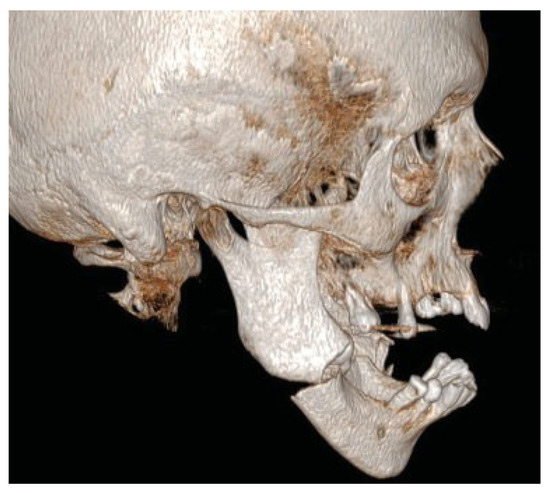

A 57-year-old man sustained a bilateral mandibular body comminute fracture due to a horse-kick trauma to his lower jaw. The subject was obese but otherwise healthy and due to the trauma omitted to the Uppsala University Hospital, Department of Oral & Maxillofacial Surgery. The anterior part of the mandible was severely displaced with a clinical open bite and the subject was taken from the Intensive care unit (ICU) to the Operating room (OR) after one night of monitoring. Partial edentulism was seen in both jaws (Figure 1). Open reduction and fixation of the fractures were performed via an intra-oral route. Noticeable was the difficulty in using a trocar due to the subjects’ constitution with abundance of soft tissue. Two mandibular plates were placed on each side and post-operative situation was evaluated with cone beam computed tomography (CBCT) (Figure 2). Initial healing was uneventful and the patient was not held in maxillo-mandibular fixation (MMF). At the two-week follow-up intraoral fistulas were found in the area of fractures and instability of the osteosynthesis occurred with opening of the bite as a result. The subject was scheduled for secondary surgery and meanwhile oral antibiotics (phenoxymethyl penicillin and metronidazole) were prescribed.

Figure 1.

Preoperative situation. Displaced bilateral mandibular body fracture after trauma by a horse-kick.